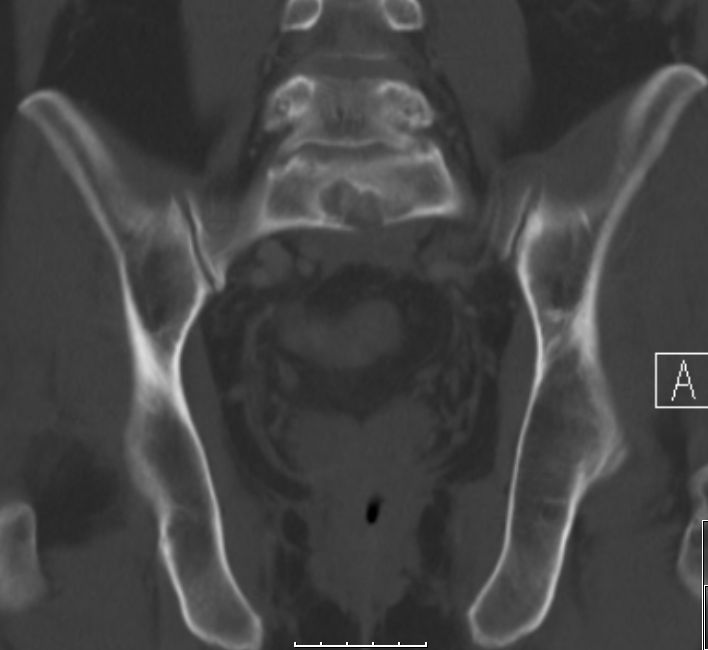

| Knochenmetastasen | 61-jähriger Patient, der vor 2,5 Jahren ein primär hepatisch metastasiertes Rektumkarzinom hatte.

9 Monate FOLFIRI/Erbitux ergaben eine CR der Lebermetastasen.

Mit verschiedenen systemischen und chirurgischen Maßnahmen Tumorkontrolle bis jetzt.

Nun Schmerzen in der linken Leiste besonders beim Treppensteigen.

Das CT zeigt eine Schambeinmetastase mit großem Weichteiltumor.![]() |

Cranial ist das symphysennahe Schambein völlig zerstört.![]() |